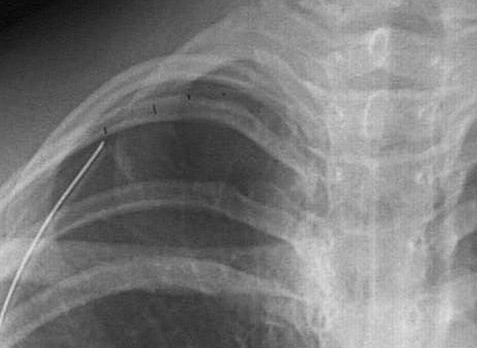

| The radiograph above demonstrates a pneumothorax on the right, with the mediastinum and heart shifted to the left. A pneumothorax results from rupture of the lung or a penetrating injury to the chest wall that allows air to enter the pleural cavity. A chest tube has been inserted here to help re-expand the lung. The faint border of the displaced visceral pleura surface is marked in the radiograph below. |